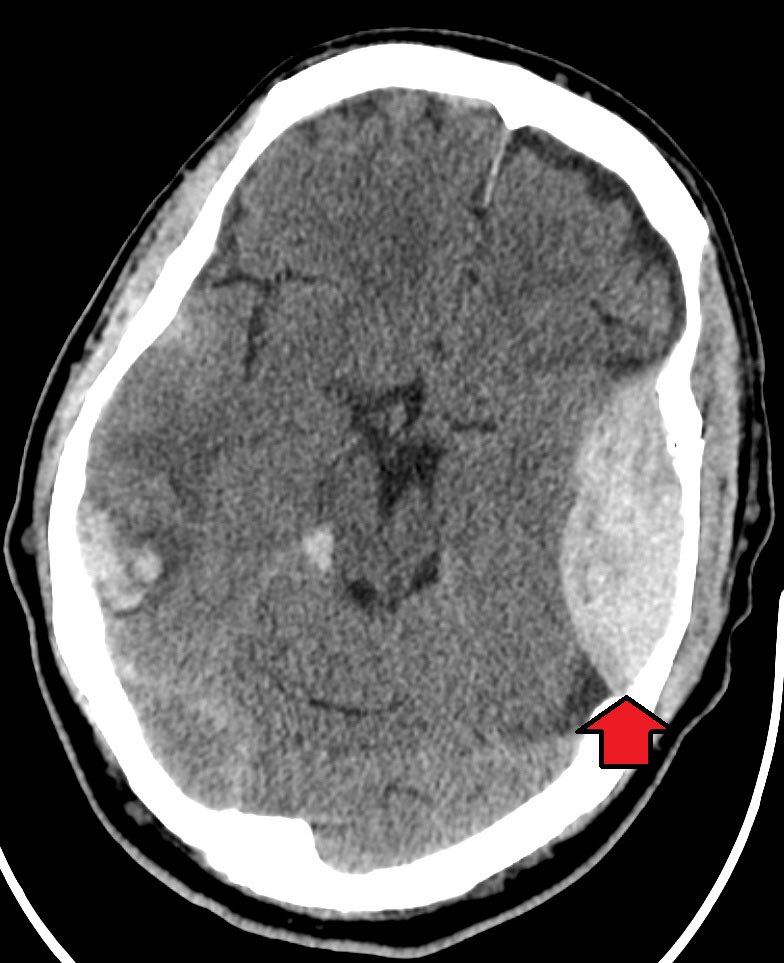

4- intraparenchymal hemorrhage

- caused by laceration of cortical parenchyma due to Contusion (coup or countercoup)

- patient may have loss of consciousness and seizures

- depends on anatomical location